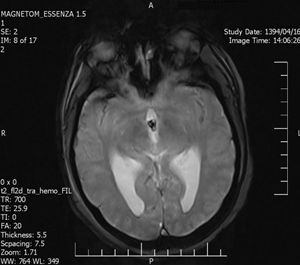

An Occipital Headache as the First Presentation of Multiple Third, Fourth, and Lateral Ventricular Cavernous Malformations: A Case Report and Review of Literature

Background: Cavernous hemangiomas are common benign vascular malformations. Their existence in the intraventricular region is very rare. Case Reports: A 43-year old woman with an occipital headache was admitted to the emergency ward. Brain computed tomography scan showed mild hydrocephalus and multiple intraventricular isodense lesions. Imaging findings, especially of Gradient Resonance Echo imaging, were in favor of multiple intraventricular cavernous malformations. Conclusion: This is a rare presentation of multiple cavernous malformation as occipital headache without needing surgical intervention in this phase. Coexistence of periventricular plaques like Radiologically isolated syndrome of Multiple sclerosis is another unique aspect in this report. [GMJ.2017;6(1):61-65]